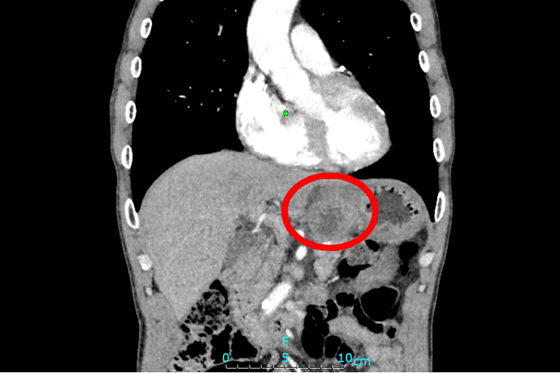

肿物位于胃与胰腺之间

廖国庆教授接诊病人后,尽快安排患者完善术前检查。增强CT等影像显示:胃小弯处肿瘤,大小约5×4cm,考虑胃恶性肿瘤,肿瘤与胰体尾部及脾动脉关系密切,不排除胰腺肿瘤可能。廖国庆教授表示:单纯行近端胃切除术可能无法完整切除肿瘤,术中可能需行联合脏器,即:近端胃+胰腺体尾部+脾脏切除术,才能将完整切除肿瘤,达到根治性切除。但手术难度大,创伤大,肿瘤包绕腹腔干,因腹腔干由腹主动脉发出,并分出胃左动脉,脾动脉,肝总动脉三支重要血管及其分支血管为胃、脾脏、肝脏、胰腺及十二指肠等重要器官供血,此处结构复杂,重要血管交错,稍有不慎极易出现大出血的情况对医患双方都是巨大挑战。经团队讨论后,结合患者一般情况,最终决定为患者实施手术治疗。术中探查也证实了术前判断,肿物与胃、胰腺及脾动脉密不可分,最终为患者实施:近端胃切除术+胰体尾部切除术+脾切除术+淋巴结清扫术。同时,采用“双通道法”为患者进行消化道重建,减少反流性食管炎及因维生素B12缺乏导致的巨幼红细胞贫血发生的可能性。